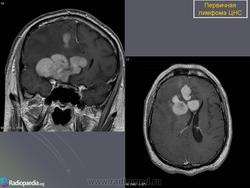

Первичные лимфомы ЦНС. Вс, 22/05/2011 - 21:45 #1 Катенёв Валенти... Не на сайте Был на сайте: 7 лет 5 месяцев назад Зарегистрирован: 22.03.2008 - 22:15 Публикации: 54876 Продолжение.Приложения:

Продолжение.